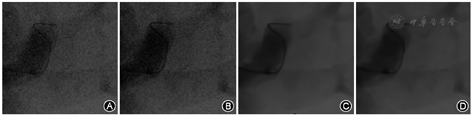

在降噪方面,DnCNN的降噪效果与我们提出的方法相当。但是在图4所示的感兴趣区域(region of interest,ROI)中,可以观察到DnCNN中的一些细节和边缘被过度平滑甚至出现模糊,从而导致细节信息的丢失,而我们提出的网络显示出可以更好地保留细节和精细结构的能力。

我们还评估了不同方法对低剂量血管造影图像的去噪效果(低剂量下曝光的剂量水平是正常剂量下的一半)。如图5和图6所示,我们还能够看到与正常剂量下的血管造影接近的图像效果。与TRF相比,DnCNN和我们提出的方法在噪声抑制方面显示出明显的优势。在TRF中,黄色矩形区域内的图像不易被识别。与DnCNN相比,我们提出的方法具有更好的细节保留和边缘锐化的能力(图6)。在低剂量血管造影中DnCNN还会出现过度平滑现象。另外,该患者AI优化前的普通参考剂量为0.25 mGy/s,优化后的辐射剂量为0.12 mGy/s,且经过本研究的AI优化后,图像质量不仅相比噪声图像得到显著改善,且与传统TRF相比,DnCNN去噪图像保留了更多的细节。TRF和DnCNN的去噪效果有限,我们提出的方法可以有效地抑制背景噪声,以及椎体或血管图像中产生的噪声[2,4]。